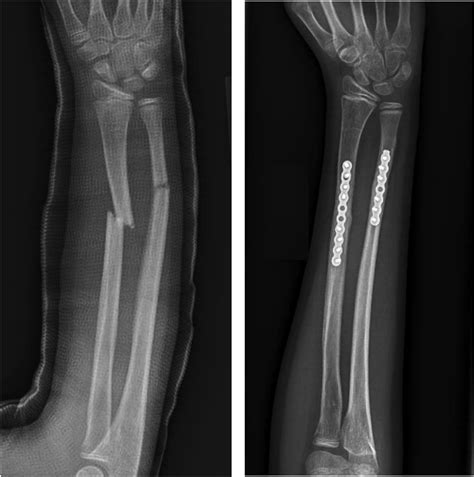

Surgical Treatment

For more severe fractures, surgery may be necessary. Surgical options include:

• Open Reduction and Internal Fixation (ORIF): This procedure involves realigning the broken bones and securing them with plates, screws, or rods.

• External Fixation: In some cases, an external fixator may be used to stabilize the bones from outside the body.